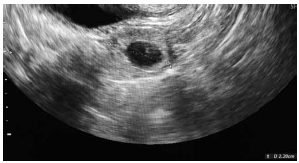

C.V.R.S., 36 anos, G VII P VI (6N) A0, IG cr: 6 semanas,deu entrada no PSGO com sangramento vaginal há cerca de 1 semana. Sem ultrassom prévio. Ao exame físico: especular: colo uterino sem lesões, mínima quantidade de sangue vermelho escuro em fórnice posterior. TV (toque vaginal) bimanual: colo impérvio, grosso, posterior. Ausência de dor à mobilização do colo uterino. Abdome: DB negativo, dor leve à palpação profunda de hipogástrio. Submetida à ultrassonografia transvaginal (imagens a seguir: figuras 1, 2, 3, 4) e beta HCG quantitativo: 9 000 UI/mL. Resultado de beta HCG 24h antes: 7 000 UI/mL.

Figura 2 (região anexial E; ovário E sem alterações)